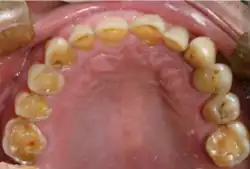

Mouth

Acid reflux into the mouth can cause breakdown of the enamel, especially on the inside surface of the teeth. A dry mouth, acid or burning sensation in the mouth, bad breath and redness of the palate may occur.[27] Less common symptoms of GERD include difficulty in swallowing, water brash, chronic cough, hoarse voice, nausea and vomiting.[26]

Signs of enamel erosion are the appearance of a smooth, silky-glazed, sometimes dull, enamel surface with the absence of perikymata, together with intact enamel along the gum margin.[28] It will be evident in people with restorations as tooth structure typically dissolves much faster than the restorative material, causing it to seem as if it "stands above" the surrounding tooth structure.[29]